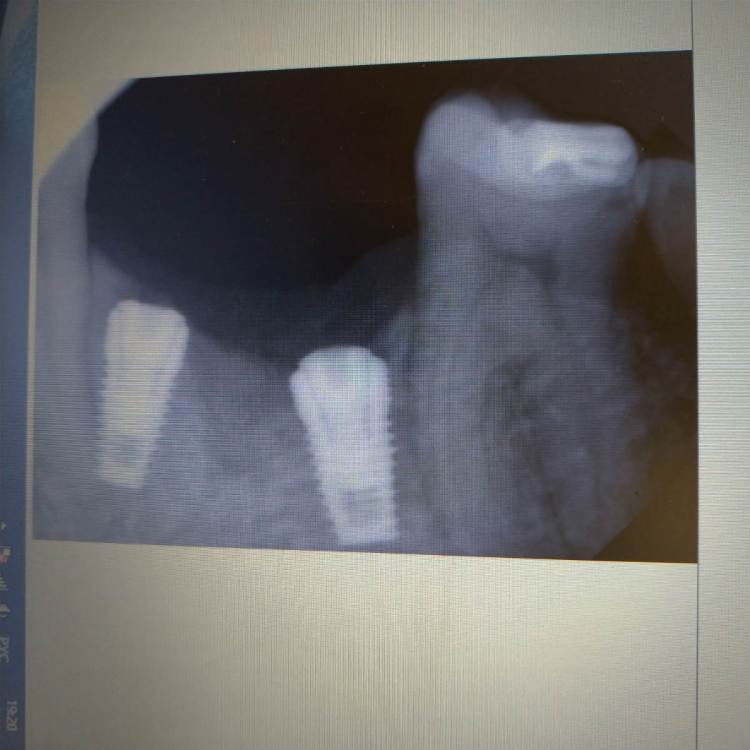

HAV Опубликовано 22 декабря, 2021 Поделиться Опубликовано 22 декабря, 2021 Всем здравствуйте. Вот такая проблема. Хотелось бы услышать мнения по дальнейшим действиям. Переустанавливать, или протезировать? Операцмя проведена несколько дней назад. Послеоперационный период без осложнений. Реакций со стороны зубов не отмечается. Всем спасибо. Ссылка на комментарий

Fin Опубликовано 22 декабря, 2021 Поделиться Опубликовано 22 декабря, 2021 (изменено) Требуется фото в полости рта желательно с пародонтальным зондом. 2д снимок очень часто не показывает достоверное расположение импланта относительно соседний зубов. Все зависит от изгиба челюсти и расположения датчика(плёнки). Так же Можно сделать несколько снимков с разным расположением датчика. Изменено 22 декабря, 2021 пользователем Fin Ссылка на комментарий

Irouil Опубликовано 22 декабря, 2021 Поделиться Опубликовано 22 декабря, 2021 Только по этим снимкам я бы удалять импланты не стал Для уточнение прогноза дальнейшего протезирования желательно сделать Компьютерную Томограмму 1 Ссылка на комментарий